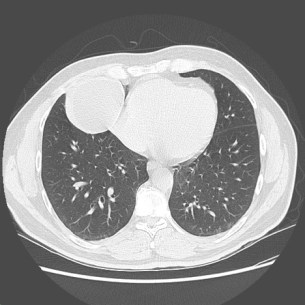

In 2013, in Canada, he presented to hospital with atypical chest pain. Chest x-ray and CT chest showed a pulmonary cystic lesion next to the right heart border.

His cardiac CT confirmed a cyst next to the heart, no evidence of coronary artery disease. He was diagnosed with a probable benign pericardial cyst. The patient was followed by the internal medicine clinic until 2014, but no formal radiological follow-up was arranged